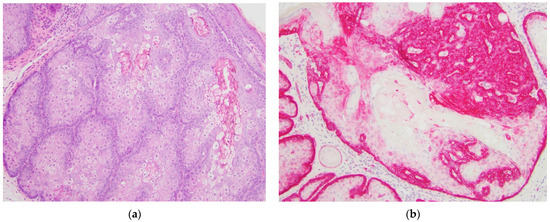

| GLUT1 Staining Pattern | Diffuse cytoplasmic and membranous staining in basaloid cells (variable) | >50% Diffuse cytoplasmic and membranous staining | <50% Diffuse cytoplasmic and membranous staining in greater than 1 layer | Only single layer of basaloid cells highlighted by GLUT1 |